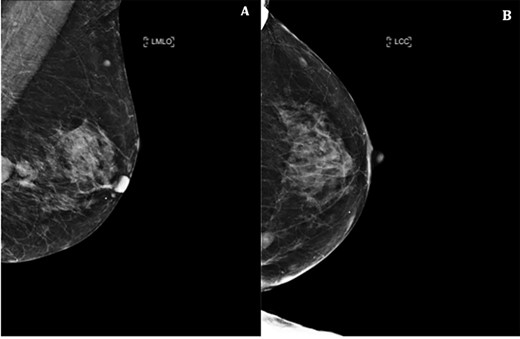

Left mammogram showing masses—A. Mediolateral oblique B. Cranial–caudal views.

Triple assessment was done—examination revealed multiple cutaneous neurofibromas in keeping her NF1. Breast examination revealed a firm irregular 2-cm lump at the 9 o’clock position of the left breast with no contralateral lumps nor any evidence of lymphadenopathy. Bilateral mammogram demonstrated a dense indeterminate mass on the left breast (Fig. 1). Targeted ultrasound scan showed two cystic-like lesions adjacent to each other (Fig. 2). A core needle biopsy was done of the larger lesion confirming grade 3 invasive ductal carcinoma—receptor status analysis revealed that the lesion was ER negative, PR negative and HER2 positive.